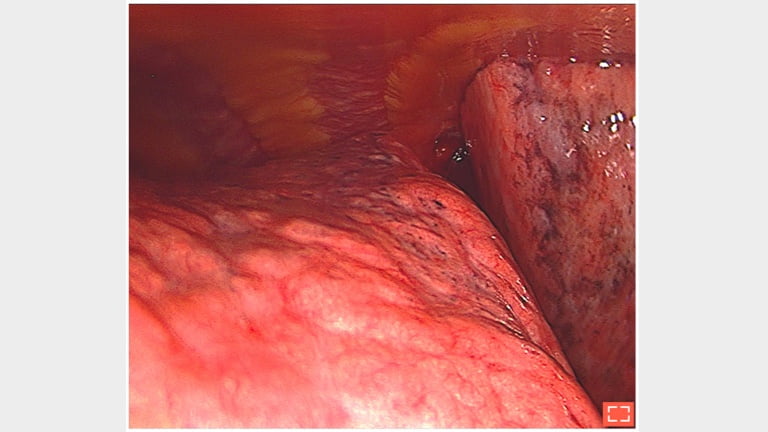

1. Thoracoscopy: micronodular pattern of lung fibrosis

fibrosis-lung